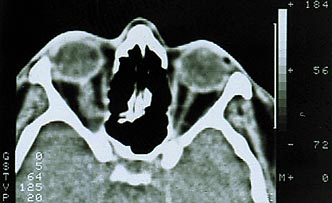

Первый тип опухоли характеризуется субдуральным ростом менингиомы вдоль ствола зрительного нерва. Частота подобного роста на нашем материале составила 41% случаев. Клинически обращает на себя внимание раннее нарушение периферического зрения с постепенным снижением центрального. В начале заболевания на фоне стойкого сужения поля зрения (концентричного или асимметричного) ухудшение центрального зрения носит интермиттирующий характер. Стойкая утрата зрительных функций наступает поздно, когда развивается атрофия диска зрительного нерва. Экзофтальм, чаще всего осевой, возникает спустя 2–3 года после появления зрительных расстройств, бывает небольшим и никогда не превышает 6–7 мм (рис. 1). Функции экстраокулярных мышц сохранены в полном объеме. Диагностировать менингиому в подобных случаях трудно даже с помощью компьютерной томографии или МРТ-исследования, так как диаметр зрительного нерва может быть увеличен незначительно (рис. 2).

Рис. 2. Компьютерная томограмма той же больной. Видна тень увеличенного зрительного нерва.